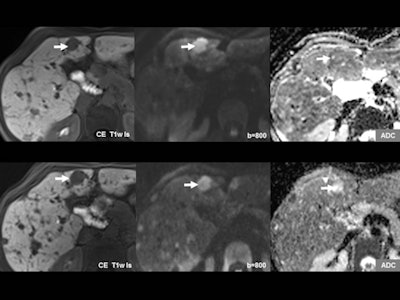

Multiparametric and quantitative imaging. Multiparametric and quantitative imaging will soon be incorporated into daily practice. Such imaging, which combines morphological information with functional, metabolic, and molecular insights, can yield a more precise assessment of diseases. Perfusion and diffusion MRI, spectral CT, and hybrid systems, such as PET/CT, are increasingly used for this purpose.

"With advanced IT technologies these imaging data can be employed for radiomics, which bring higher precision in diagnosis, assessment of prognosis -- for example, disease-free survival in tumor patients -- and selection of appropriate therapy, such as the most effective drugs in cancer therapy. With diffusion-weighted imaging [DWI] the aggressiveness of prostate cancer can be predicted, facilitating the choice of whether to perform aggressive treatment or to wait and see," Reiser said. "Imaging results should be measured quantitatively. It's not enough to say, for example 'strong diffusion restriction.' Whenever possible we should put a number on it."